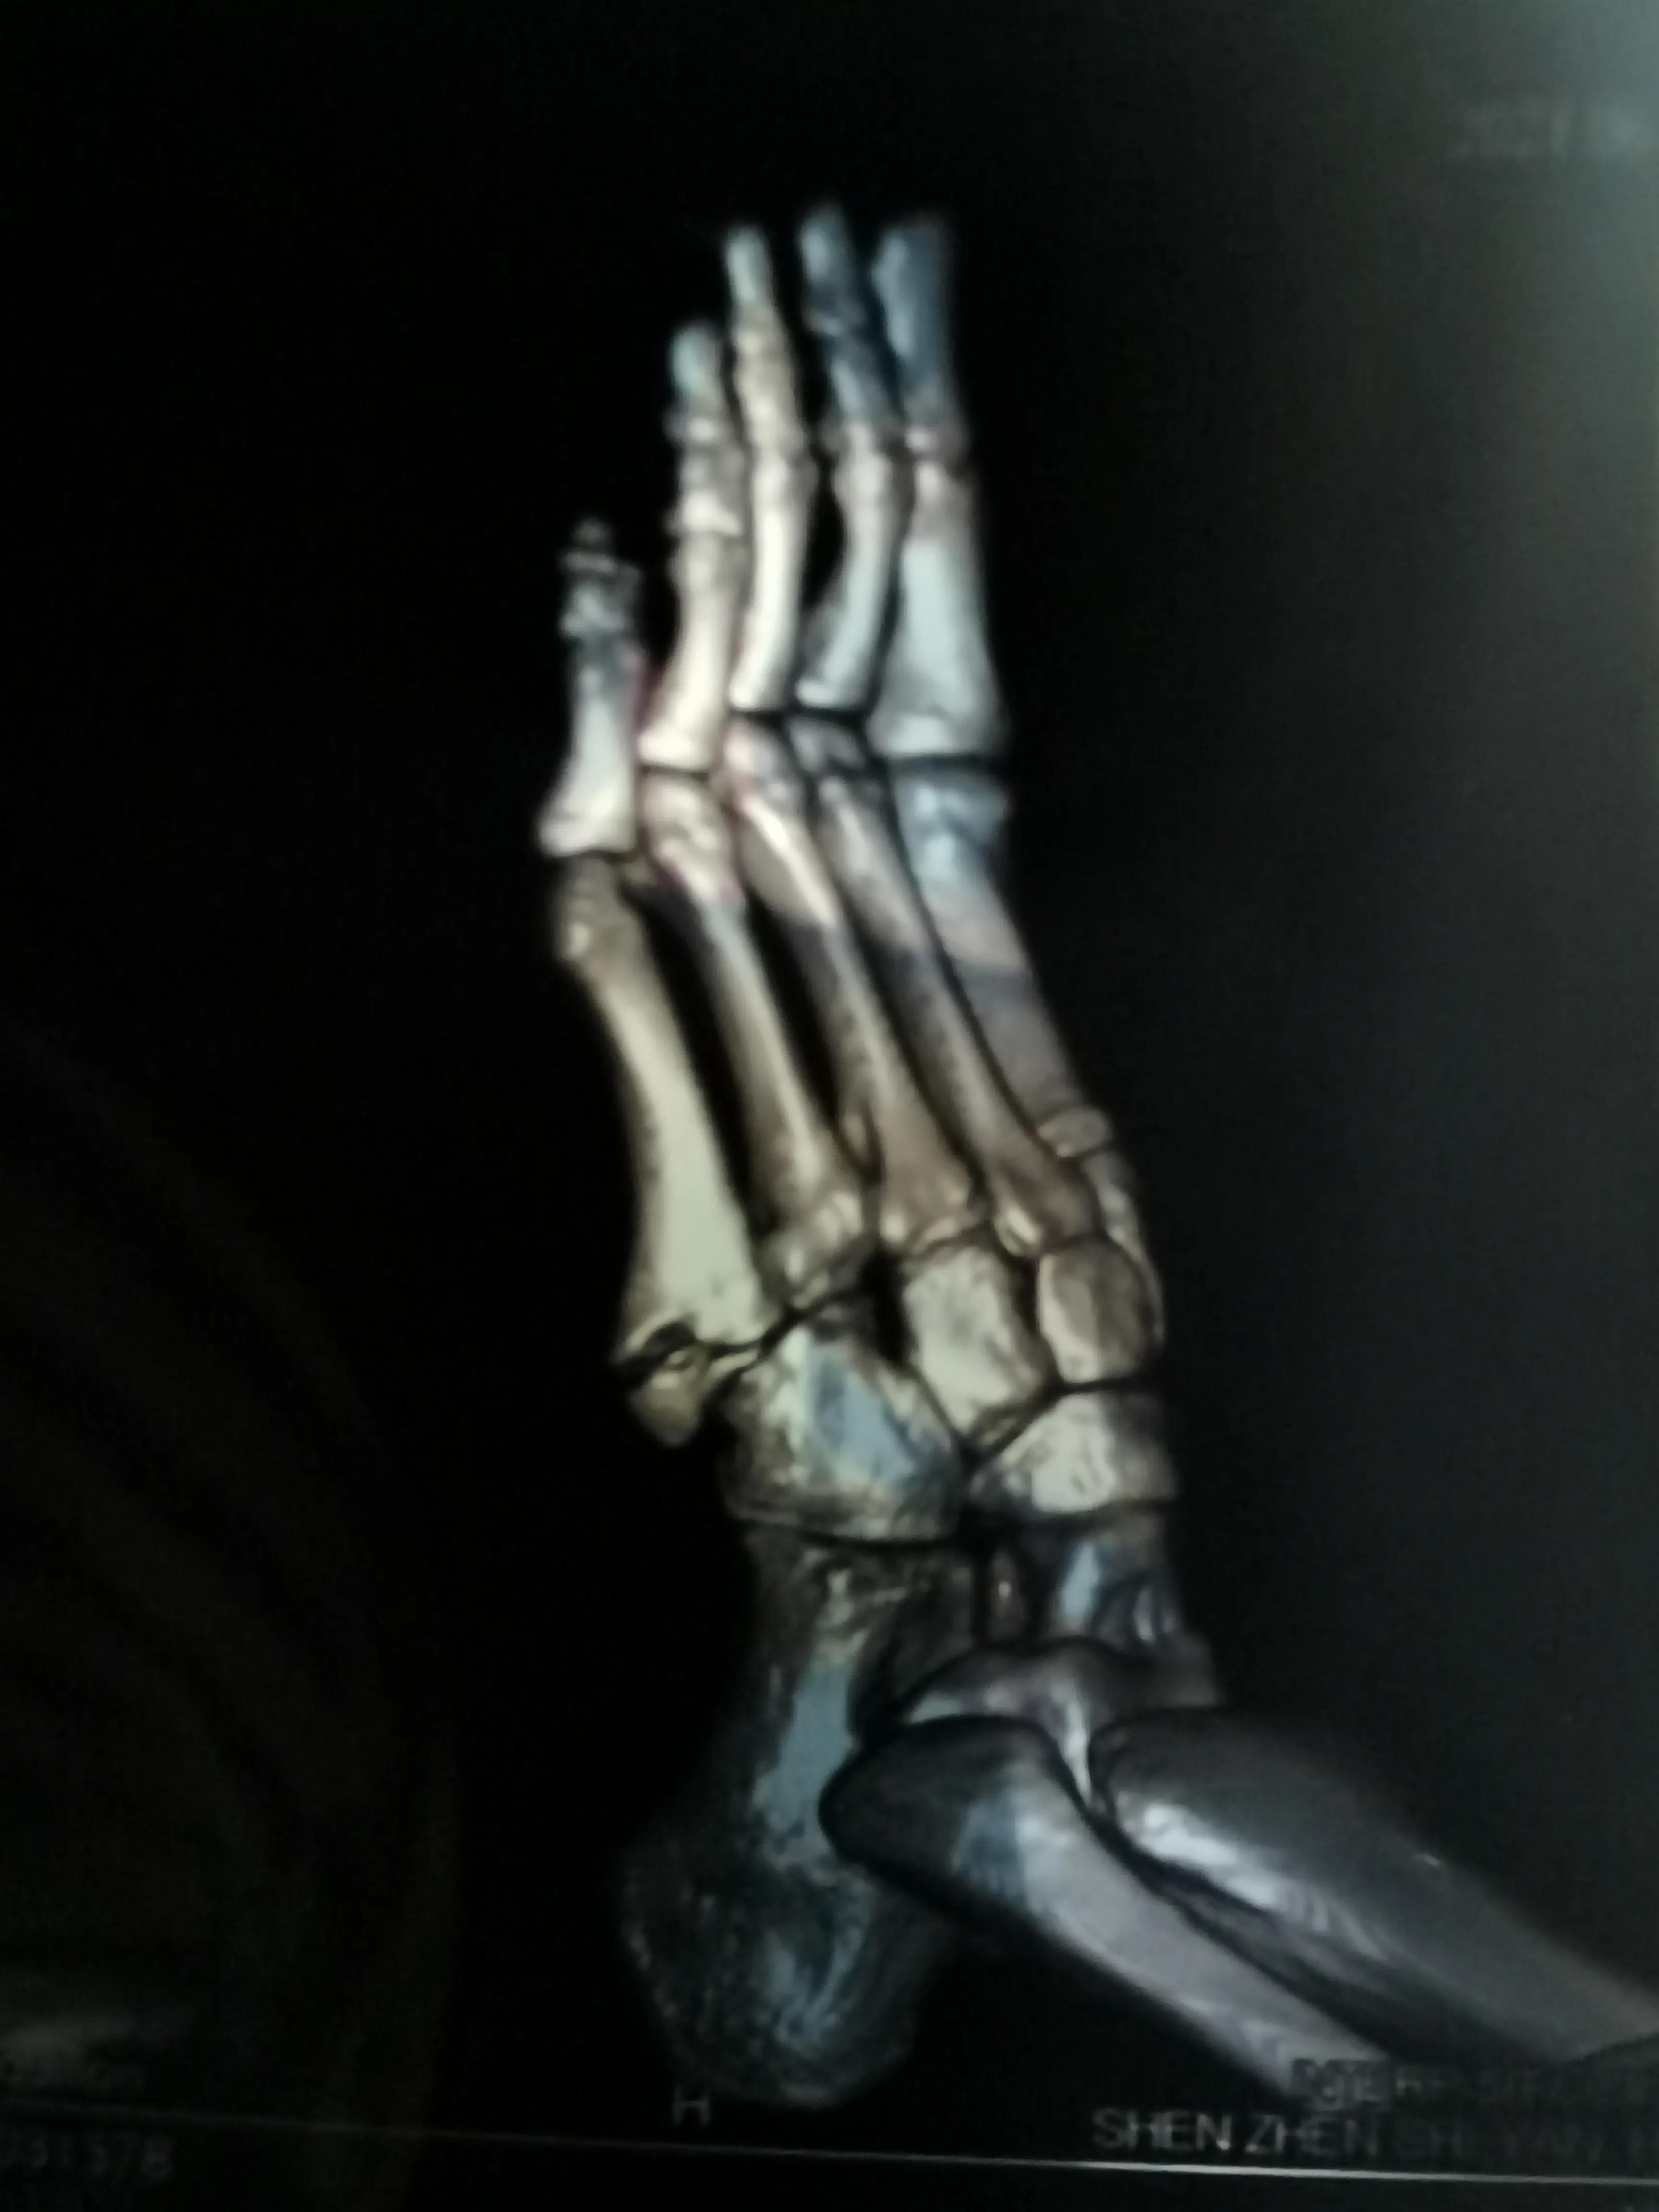

看片子骨缝比较大了,有点移位,而且中间崩碎了一块,一直找不到,后来复查才发现那个碎片掉落在骨缝当中了

此图可以看见中间碎片在骨缝里面

仔细研究一下,这个位置属于足弓的一部分,肌腱附着比较多,挺重要的